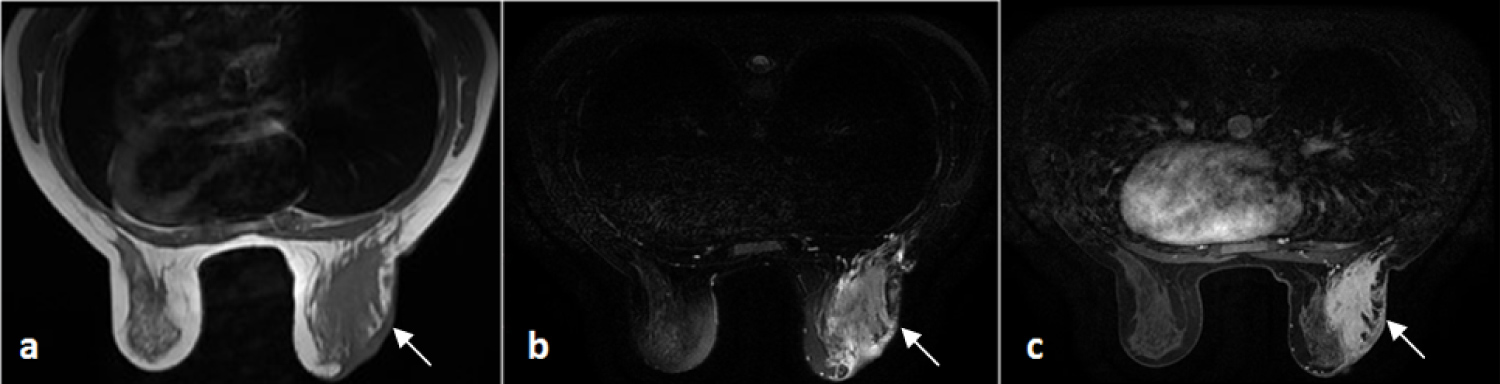

The mammography showed a dense ill-defined opacity in the outer quadrants of the right breast. The mammary ultrasound pointed out an irregular ill-defined mass in the junction of the outer quadrants of the right breast, measuring approximatively 51 × 25 mm. It was hypoechoic, heterogeneous and non-attenuating, it also had a starting fistulous opening through the subcutaneous tissue in the peri-mammillary region, and was associated to a diffuse fatty infiltration and some inflammatory looking ipsilateral adenomegalies with a fatty hilum. The MRI was in favor of a right mastitis (Figure 2).

Figure 2: Axial sections in T1-weighted scanning sequences (a) T2; (b) After injection; (c) Showing a right mammary infiltration that's isointense T1, hyperintense T2 and strongly enhanced after injection, associated to a skin thickening, a mammillary retraction and ipsilateral axillary adenopathy. View Figure 2